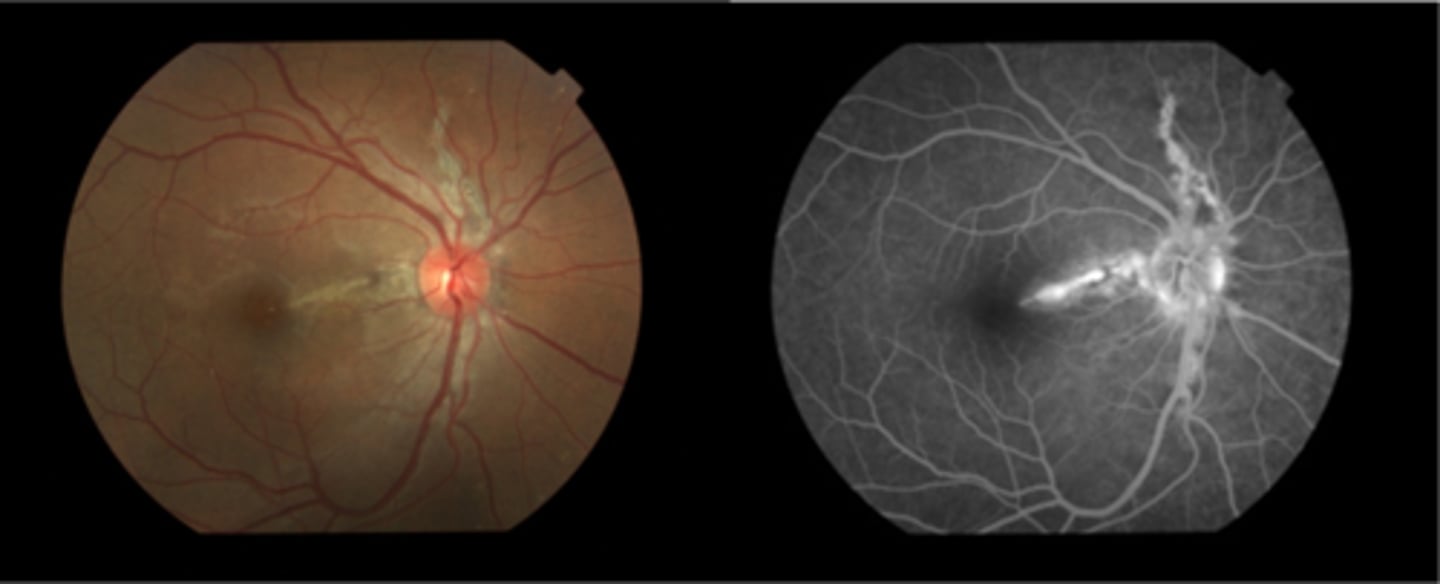

What are angioid streaks and what type of atrophy do they lead to?

breaks in Bruch's membrane in a radiating fashion emanating from the ONH = leads to RPE, PR's, choriocapillaris atrophy

What causes angioid streaks?

weakened, calcified Bruch's membrane, often in connective tissue disease = bilateral

How does angioid streaks appear on IVFA?

hyperF bc loss of RPE = can see choroid better

How does angioid streaks appear on FAF?

hypoAF bc RPE loss/damage

What ONH finding is sometimes seen with angioid streaks?

disc drusen